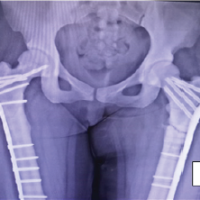

Under tourniquet, through a dorsal midline approach, en bloc resection of the lobulated mass followed by extended curettage of surrounding tumor tissue was performed (Fig. 2), including removal of soft-tissue components between dorsal extensor compartments and careful protection of the flexor sheath and Median nerve volarly.

Figure 2: Intra-operative clinical image depicting the main lobulated mass being excised (top left); intra-operative clinical image after en bloc excision, iliac crest bone grafting, and stabilization with four K-wires. (top right); immediate post-operative antero-posterior radiograph of the wrist (bottom left); histopathological photomicrograph depicting the pathological spindle-shaped stromal cells and multi-nucleated giant cells (bottom right).

Residual cavity margins were curetted to punctate bleeding and burred, followed by application of 2 × 1-min cycles of hydrogen peroxide, while protecting surrounding soft tissues with moist gauze. A structural tricortical iliac crest autograft was fashioned to restore the distal carpal row and achieve normal carpal height, and a morselized cancellous bone graft was packed after debriding the distal cartilaginous surfaces of the proximal carpal bones to permit graft integration. Stable fixation was achieved with two smooth K-wires from the radius and ulna in a criss-cross fashion across the reconstructed column and attaining strong cortical purchase in the metacarpal shafts, one K-wire in retrograde direction from the 2nd metacarpal to the ulna, and one K-wire in retrograde direction from the 4th metacarpal base across the graft to the scaphoid (Fig. 2).